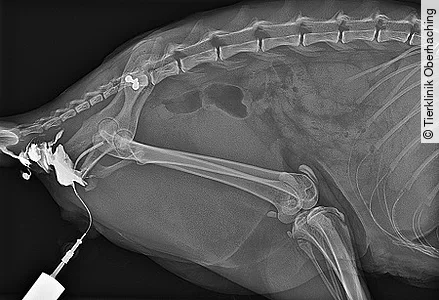

Neben Röntgenaufnahmen des Beckens in 2 Ebenen sind Röntgenbilder des Thorax unerlässlich. Aufgrund der Dolenz sind gestreckte ventrodorsale Röntgenaufnahmen der Hüfte häufig auch nach Opiatgabe kaum durchzuführen. Für eine erste Einschätzung kann eine leicht aufgehockte Aufnahme in Frosch-Position sehr hilfreich sein und wird von den Patienten bei sanfter Manipulation oftmals gut toleriert.

Abbildung 1 - Röntgenaufnahme des Beckens in Frosch-Position.

a Aufgehockte Lagerung für eine initiale ventrodorsale Beckenaufnahme in Frosch-Position.

b Keine perfekt gerade Röntgenaufnahme, aber für den Patienten wach auszuhalten und sehr gut geeignet, um eine erste Übersicht über das Ausmaß der Verletzungen zu gewinnen. Eine sauber gelagerte, gestreckte Aufnahme erfolgt dann in Narkose vor der Frakturversorgung.